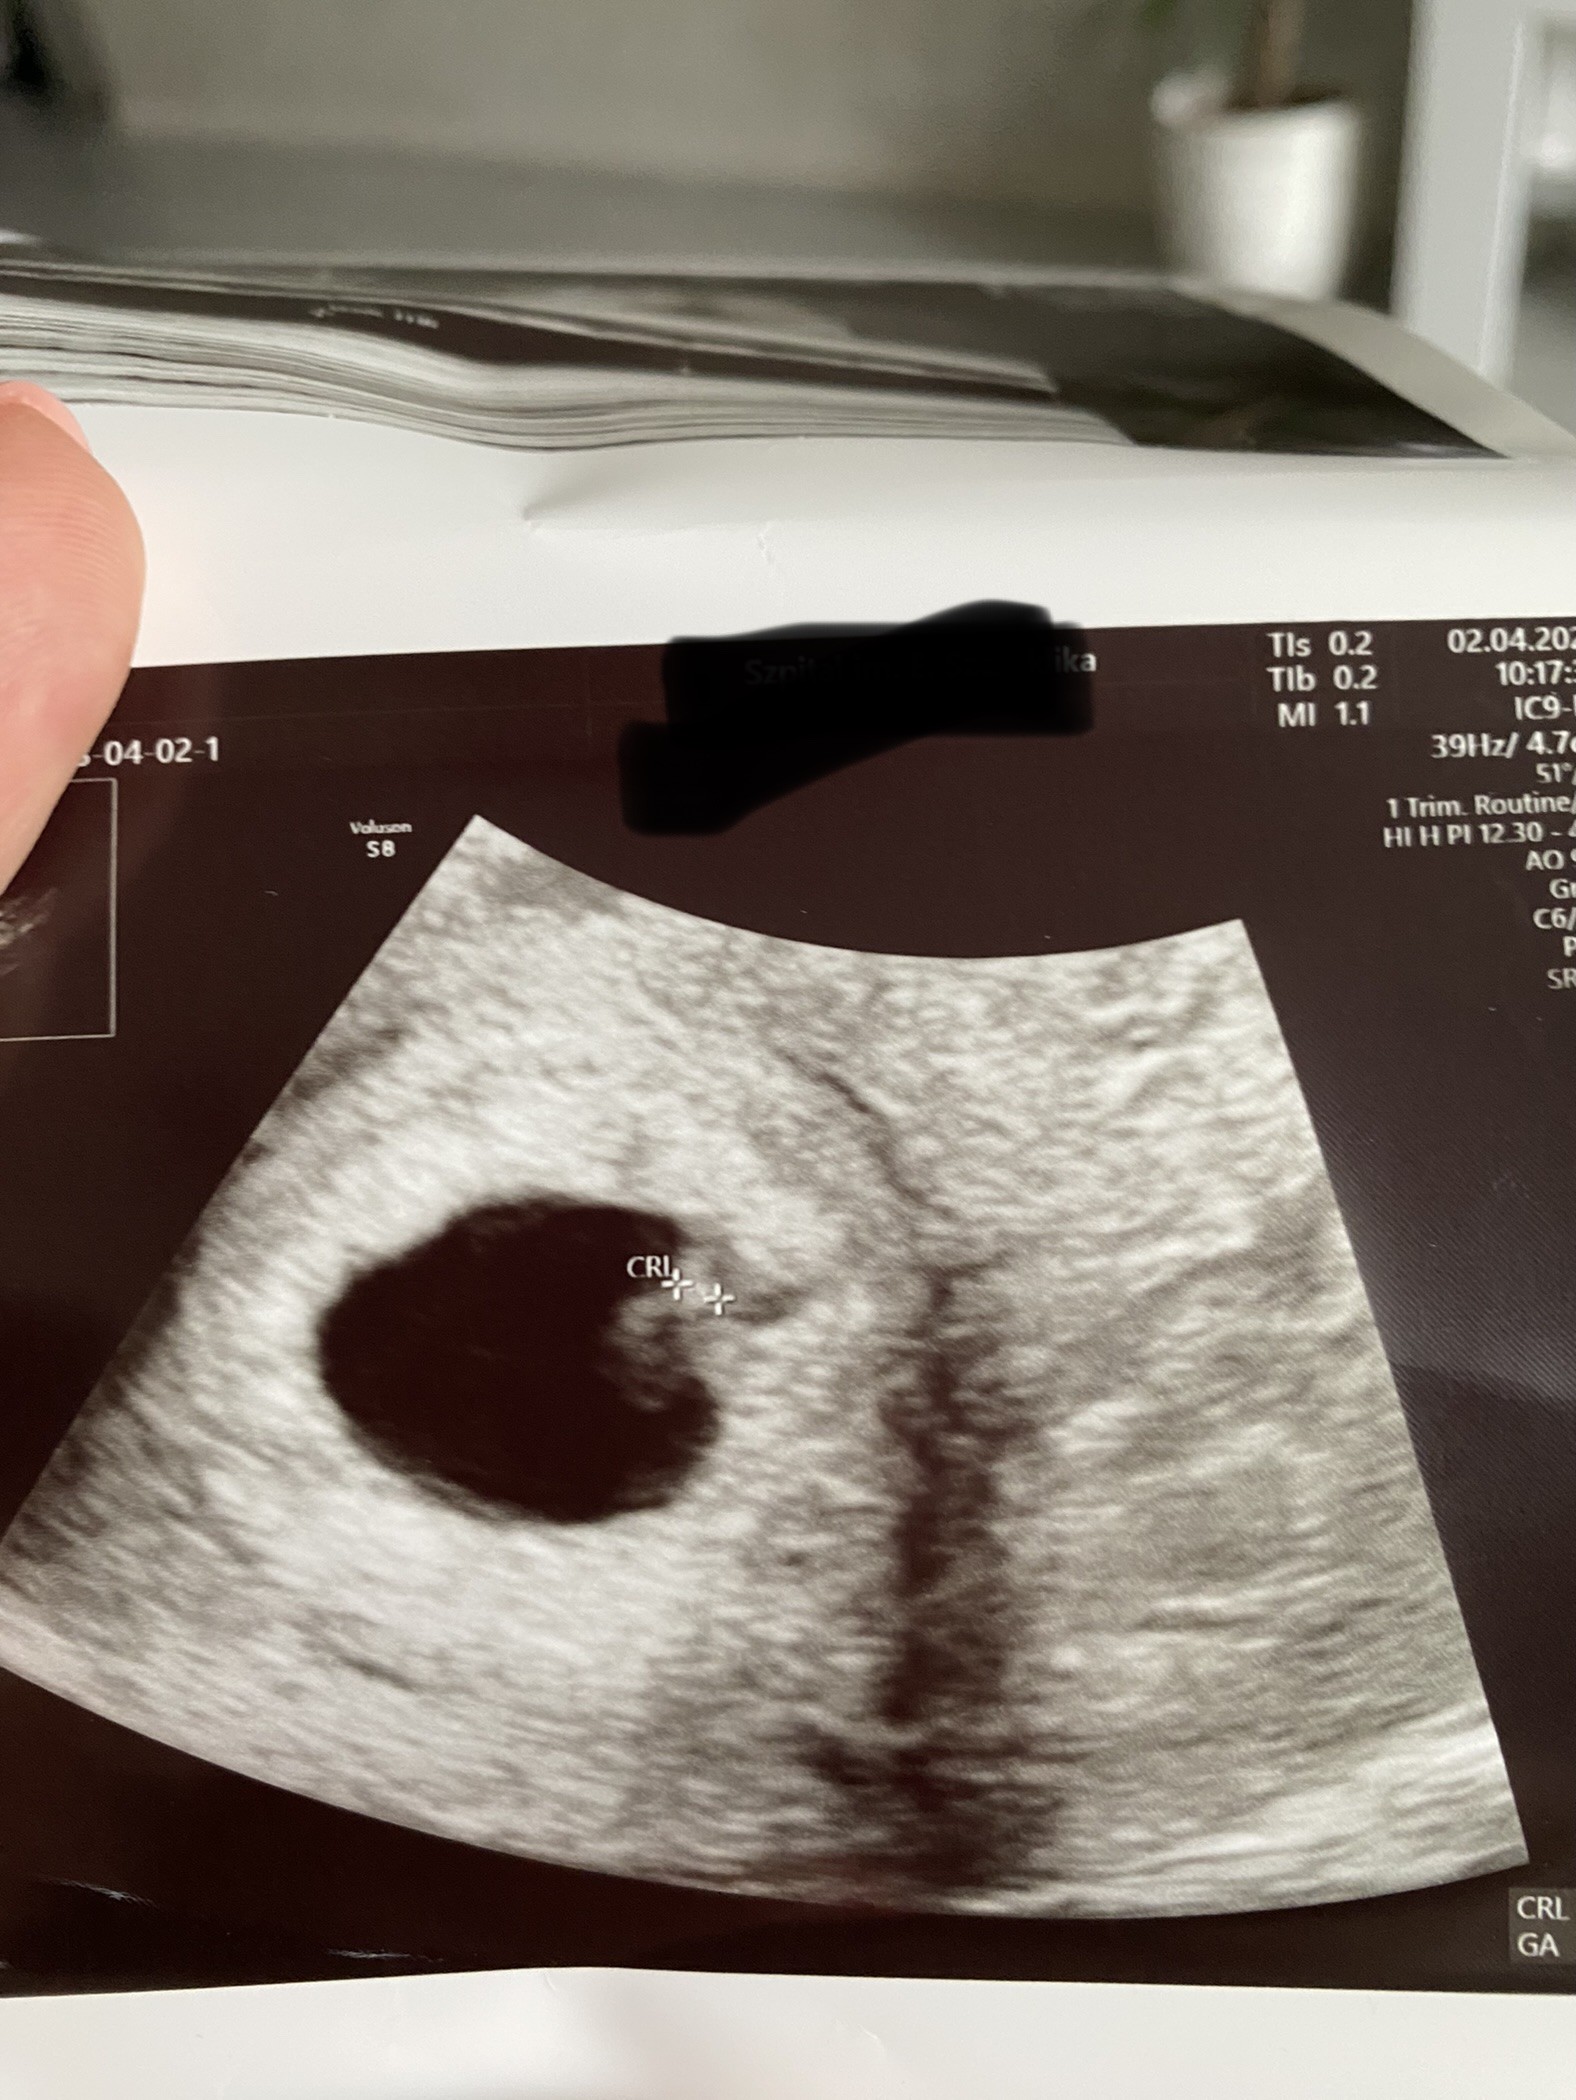

Dziś 22dpt i mamy serduszko ♥️

Przedstawiam Wam moją kluseczkę która już od kilku dni daje matce ostro popalić …🤢🤮😵‍💫🤯😊

Załączniki

• IMG_2751.jpeg

IMG_2751.jpeg

557,7 KB · Wyświetleń: 122